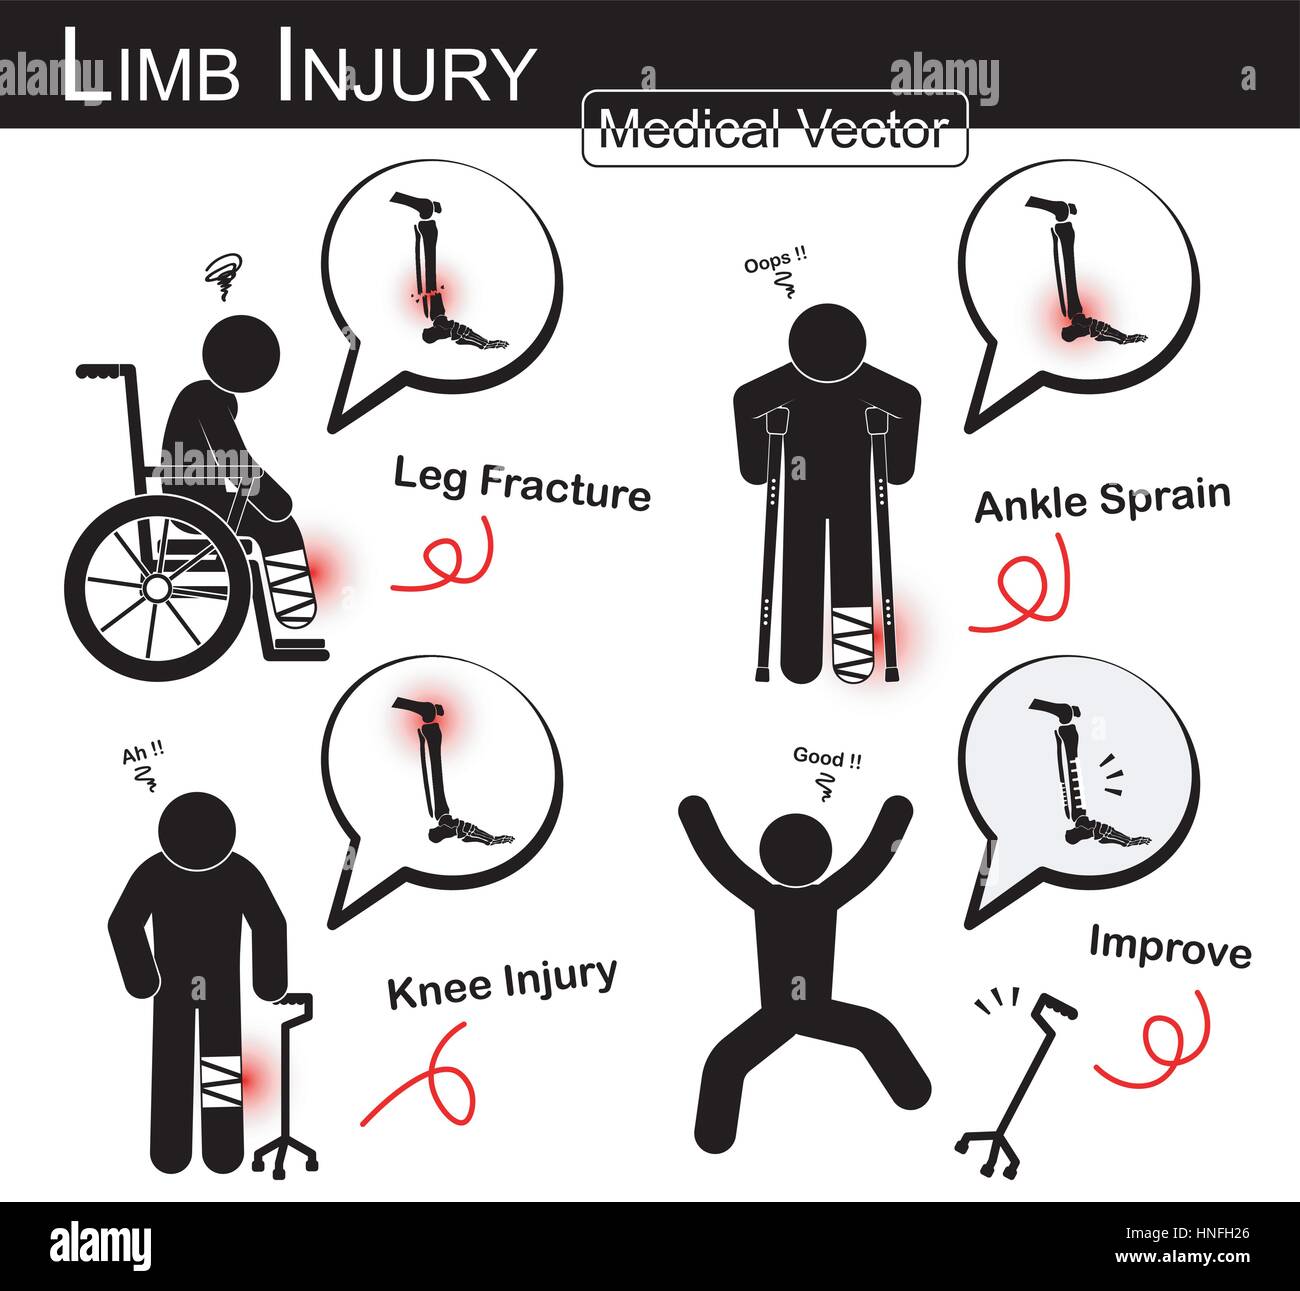

Série de blessures des membres supérieurs ( stick man avec béquille axillaire , fauteuil , canne trépied ) ( Fracture du tibia et du péroné , l'entorse de la cheville au genou , arthralgies )( vect Illustration de Vecteurhttps://www.alamyimages.fr/image-license-details/?v=1https://www.alamyimages.fr/photo-image-serie-de-blessures-des-membres-superieurs-stick-man-avec-bequille-axillaire-fauteuil-canne-trepied-fracture-du-tibia-et-du-perone-l-entorse-de-la-cheville-au-genou-arthralgies-vect-133723022.html

Série de blessures des membres supérieurs ( stick man avec béquille axillaire , fauteuil , canne trépied ) ( Fracture du tibia et du péroné , l'entorse de la cheville au genou , arthralgies )( vect Illustration de Vecteurhttps://www.alamyimages.fr/image-license-details/?v=1https://www.alamyimages.fr/photo-image-serie-de-blessures-des-membres-superieurs-stick-man-avec-bequille-axillaire-fauteuil-canne-trepied-fracture-du-tibia-et-du-perone-l-entorse-de-la-cheville-au-genou-arthralgies-vect-133723022.htmlRFHNFH26–Série de blessures des membres supérieurs ( stick man avec béquille axillaire , fauteuil , canne trépied ) ( Fracture du tibia et du péroné , l'entorse de la cheville au genou , arthralgies )( vect

Série de blessures des membres supérieurs ( stick man avec béquille axillaire , fauteuil , canne trépied ) ( Fracture du tibia et du péroné , k , entorse de cheville Banque D'Imageshttps://www.alamyimages.fr/image-license-details/?v=1https://www.alamyimages.fr/photo-image-serie-de-blessures-des-membres-superieurs-stick-man-avec-bequille-axillaire-fauteuil-canne-trepied-fracture-du-tibia-et-du-perone-k-entorse-de-cheville-84620773.html

Série de blessures des membres supérieurs ( stick man avec béquille axillaire , fauteuil , canne trépied ) ( Fracture du tibia et du péroné , k , entorse de cheville Banque D'Imageshttps://www.alamyimages.fr/image-license-details/?v=1https://www.alamyimages.fr/photo-image-serie-de-blessures-des-membres-superieurs-stick-man-avec-bequille-axillaire-fauteuil-canne-trepied-fracture-du-tibia-et-du-perone-k-entorse-de-cheville-84620773.htmlRMEWJPJD–Série de blessures des membres supérieurs ( stick man avec béquille axillaire , fauteuil , canne trépied ) ( Fracture du tibia et du péroné , k , entorse de cheville